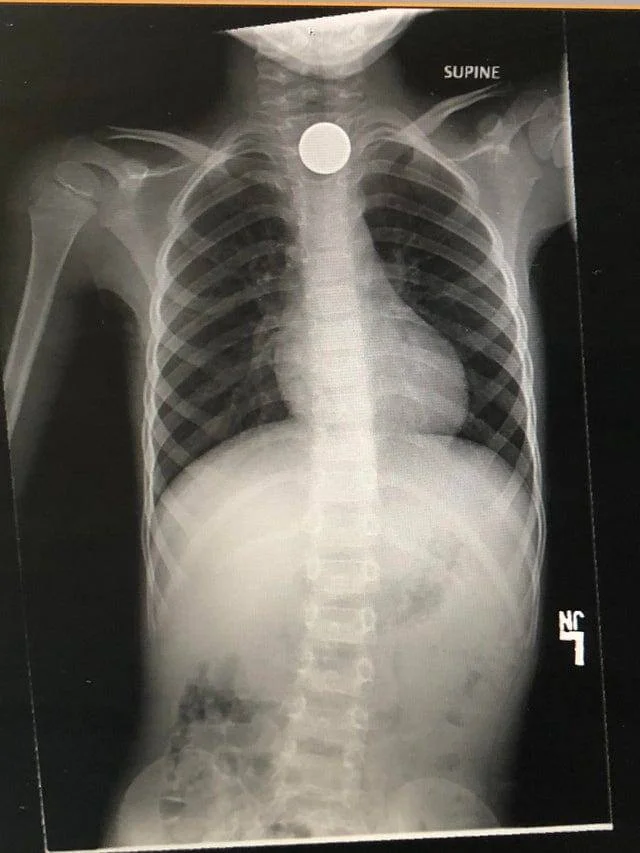

17. Мой сын решил проглотить монетку и превратил её в огромный счёт от врача